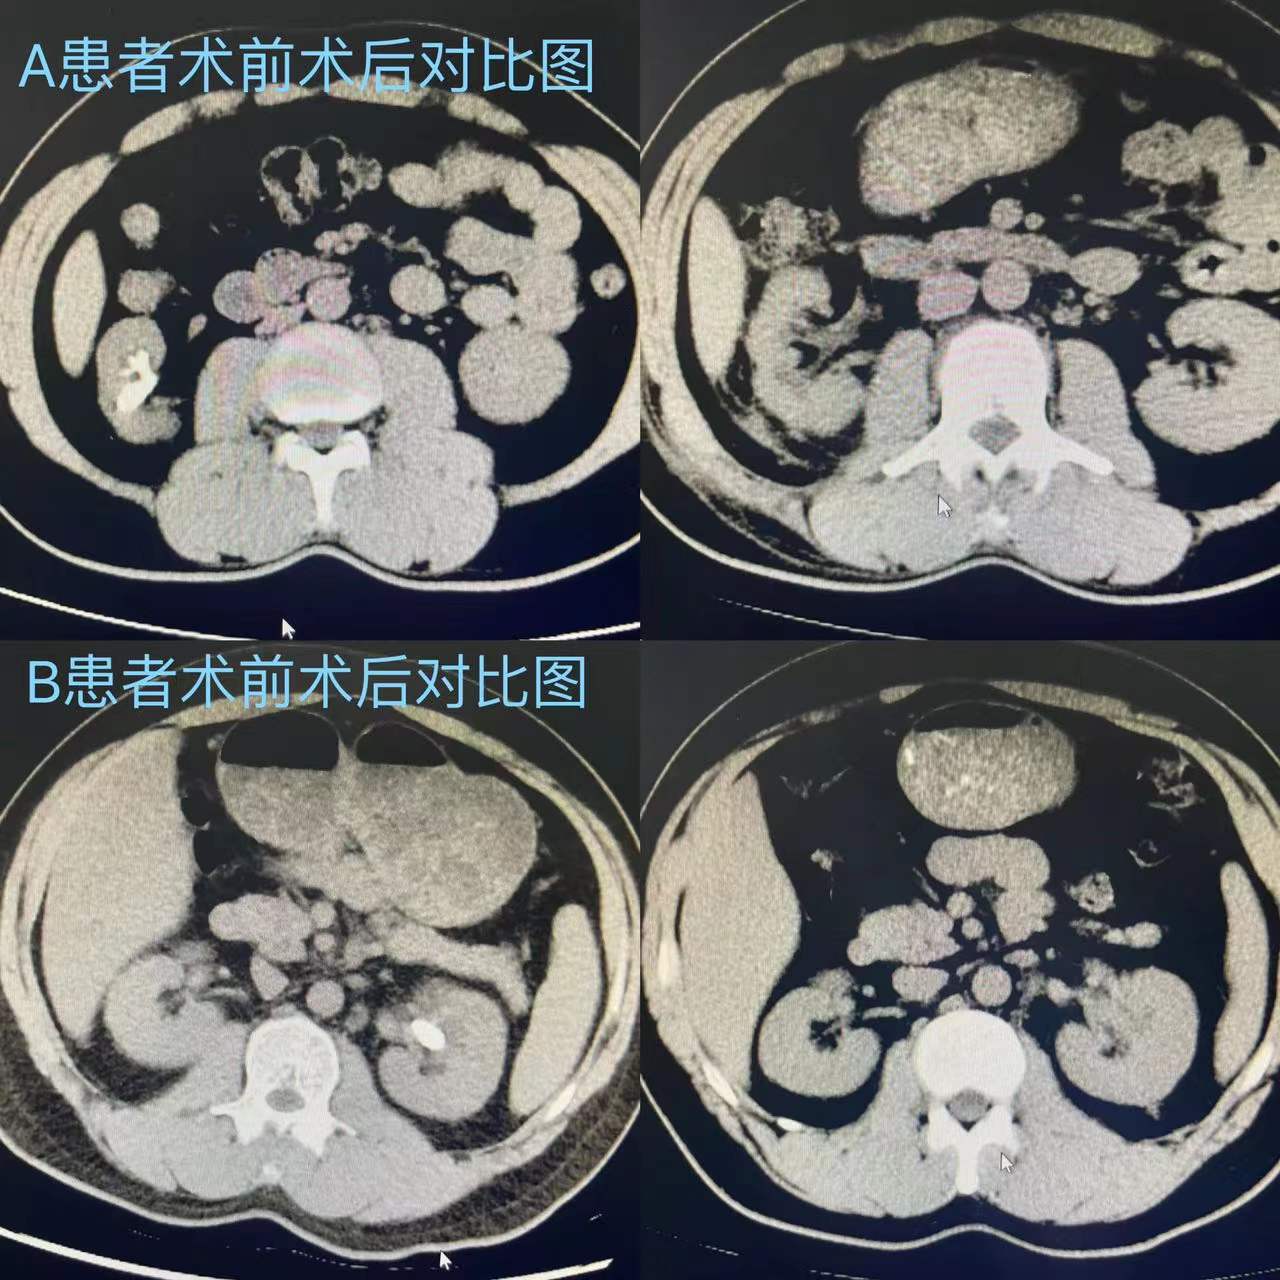

目前,两位患者均已完成术后 CT 复查,结果显示:已取净结石,肾周无血肿渗出。患者出院时表示,围术期的全过程是一次特殊的“享受”,无痛的手术享受,细心耐心的诊疗享受,干净舒适的住院享受。尹光明表示,外科医生一辈子站在手术台上,非常希望每一台手术都能解决患者躯体疾病,能在确保患者生命安全前提下不断开展新技术,让技术的提升更好地助力患者术后的康复,让手术不再痛苦而是“享受”就最好不过了。

伴随医疗技术的发展,传统的开放性取石手术早已被输尿管镜碎石或经皮肾镜碎石术取代,该术式具有创伤小、恢复快的绝对优势,但术后医生会在患者输尿管内常规留置双“J”管支撑,经手术造瘘口留置肾造瘘管进行体外引流,部分患者因管道留置会伴有不同程度的不适感。2月10日,尹光明为两位患者进行了经皮肾镜取石术,通过小通道微创经皮肾镜钬激光碎石取石手术顺利完成取石,术中无明显出血,结石清除效果满意,且两位患者术后均未留置任何管道,即无输尿管支架管,无肾造瘘管,做到了真正的“无管化”,该手术方式让泌尿系结石“打孔取石”术后患者的舒适感得到明显提升,特别是术后疼痛明显减轻。据悉,“无管化”操作是近几年结石系结石专家关注的热点,但真正实现“无管化”操作却相对少见,不放置肾造瘘管避免其意外牵拉引起的术后大出血,可明显减轻患者疼痛,减少患者的感染风险、降低住院时长及住院费用;不放置双“J”管则可避免患者置管后出现尿频、尿急、血尿等症状,还免去了术后拔除双“J”管的过程,减轻患者身心和经济负担。同时,“无管化”经皮肾镜对术后快速康复有重要意义,是将“打洞取石”手术转成日间手术的一个重要技术保障。